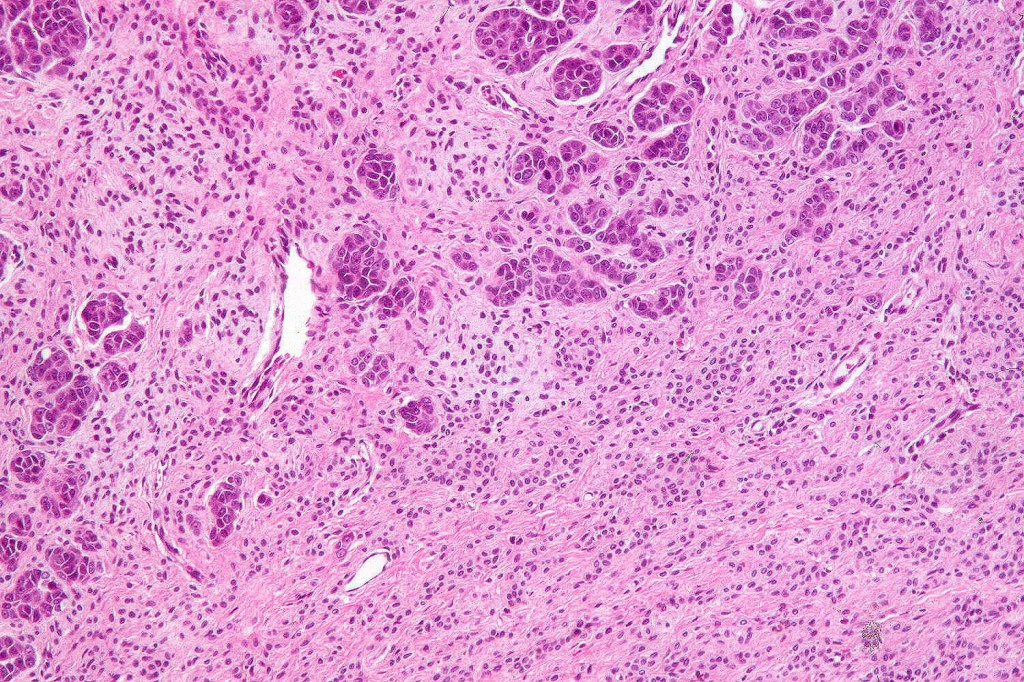

•It is hypercellular and most often composed of epithelioid cells showing little pleomorphism & only occasional mitoses

•Nuleoli are small

•Intracytoplasmic pseudo-inclusions

•The constituent cells are generally larger than the adjacent nevus cells

•Some examples show more marked pleomorphism with prominent nucleoli and increased mitotic activity but abnormal mitoses are not a feature. These are not associated with any sinister biological potential